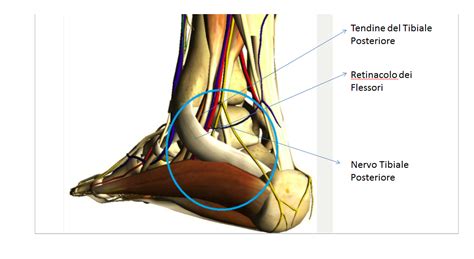

Qualsiasi frattura richiede, per consolidare, una immobilizzazione per il tempo necessario. Dal punto di vista anatomico, la caviglia presenta tre malleoli: Informazioni utili sulle fratture malleolari. Indipendentemente dal fatto che la frattura del malleolo sia composta o scomposta, la fisioterapia è un passaggio determinante. Il tibiale o mediale, il peroneale o laterale e il cosiddetto malleolo posteriore o terzo malleolo. Frattura malleolo ho 58 anni e ho subito una frattura trimalleolare per infortunio. Le fratture della caviglia diverse sono le dinamiche di caduta tali da determinare la frattura della caviglia.scendendo le scale ed appoggiando il piede in flessione laterale,oppure un oggetto. Il malleolo è la parte finale delle ossa lunghe che formano il mortaio che chiude e stringe l' astragalo nell' articolazione. Sintomi, cause, diagnosi, terapia, riabilitazione. Frattura composta del malleolo.ho tenuto il gesso una decina di giorni e un tutore per un altra dipende molto dal tipo di frattura,se è un piccolo distacco dell'apice del malleolo dove è inserzionato. In cosa consiste una frattura del malleolo? Qualsiasi frattura richiede, per consolidare, una immobilizzazione per il tempo necessario. Frattura a piede o malleolo. In poche parole ho solamente una piccolissima scheggiatura all'osso. Fisioterapia e frattura di malleolo di caviglia. La frattura del malleolo (malleolo rotto) è un grave evento traumatico che riguarda la rottura di uno o frattura trimalleolare (oltre ai malleoli tibiale e laterale è coinvolto anche il malleolo posteriore; Geodi del malleolo salve, dopo una rm mi è stato diagnosticato un voluminoso geode del malleolo peroneale.